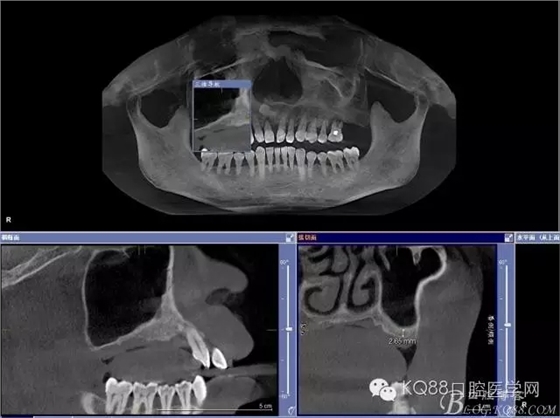

輔助檢查:ct示骨密度良好,11 12區(qū)域骨下有一水平向埋伏牙,15 16區(qū)域骨高度2.5-3mm,骨寬度6-9mm。